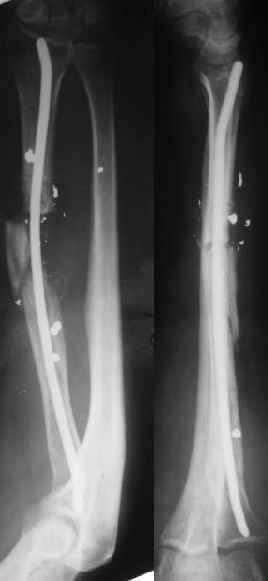

В приложении - снимок по окончании дистракции, и после смены аппарата на стержень (довольно толстый, 5 мм). С входом в канал на центральном отломке пришлось малость попотеть, промежуточный отломок его прикрывал. Но все-таки удалось закрыто проколупать. Надеюсь, дня через 3-4 после операции можно будет передать пациента нейрохирургам. Буду признателен за критику и комментарии.

Все за и про интрамедуллярной фиксации этого перелома луча уже обсуждались - все идет по плану.

Твоя концепция стабилизации отломков, своего рода *протезирования* лучевой кости продемонстрирована на Ргграммах. Прямого кость-кость контакта между дистальным и промежуточным фрагментами не получилось, что может скомпрометировать сращение перелома, хотя при первично стабильной фиксации и сохраненной надкостнице можно рассчитывать не

формирование периостальной мозоли (видимо этот механизм и работал в твоих прежних случаях).